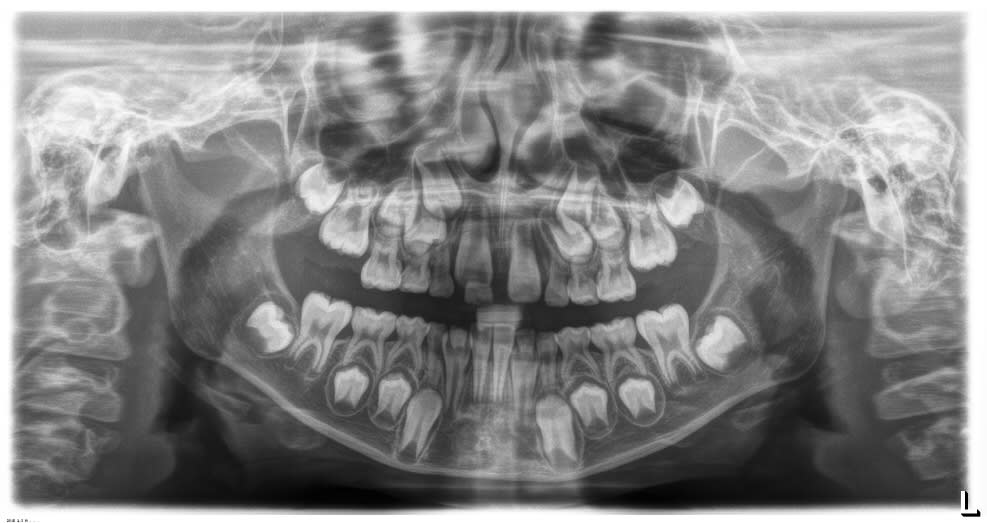

Gamine, 7 ans, vue en consult d'odf car le papa s'inquiète de "l'espace entre les 2 dents de devant".

Du coup, pano, agénésie de 12/22.

Les 23 / 24 m'inquiètent ..